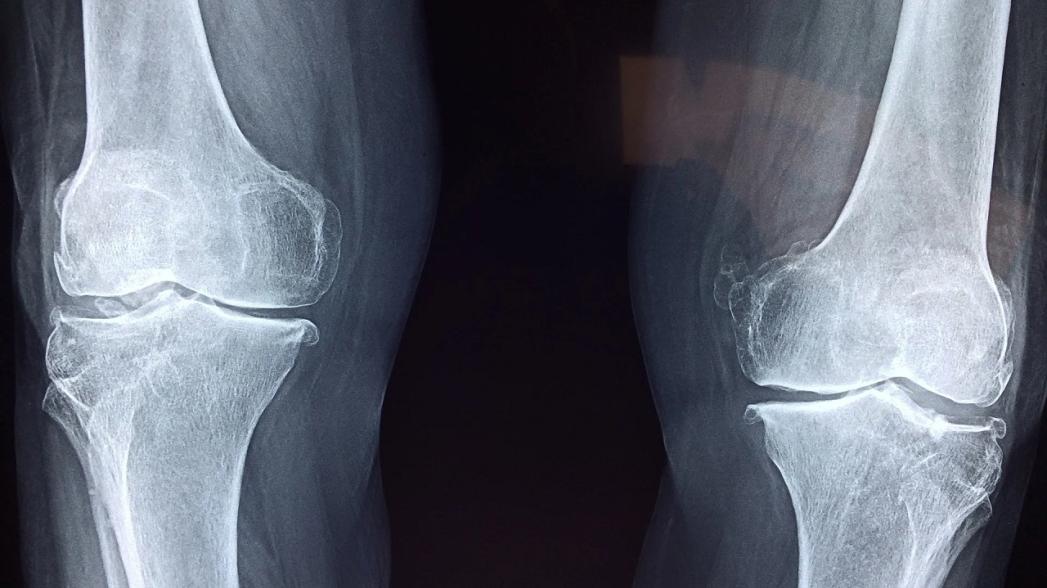

Французская компания Gleamer получила разрешение американского регулятора (FDA) на использование системы BoneView, которая автоматически выявляет переломы костей и травматические повреждения верхних и нижних конечностей, а также в грудной клетке и позвоночнике.

Эта система на базе технологии искусственного интеллекта, предназначенная для анализа рентгеновских снимков, ранее уже была сертифицирована в Европе.

Специалисты компании заявляют, что их компьютерная диагностическая система призвана помочь врачам скорой помощи, хирургам-ортопедам, ревматологам и семейным врачам в быстрой оценке рентгеновских снимков. После обнаружения перелома платформа Gleamer расставляет приоритеты и отправляет свои выводы радиологу для подтверждения.

В ходе исследования, в котором были собраны снимки из нескольких медицинских центров США и от специалистов, использующих самые разные рентгеновские аппараты, программа искусственного интеллекта BoneView показала, что она может помочь снизить частоту незамеченных переломов почти на 30%.